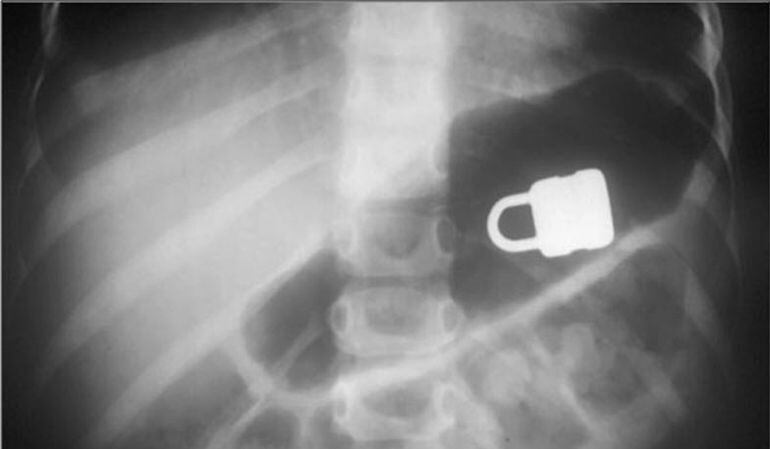

Els radiòlegs catalans comencen demà el seu congrès , dedicat a la radiologia d’urgències. Una de les situacions més habitual d’aquests especialistes és la intervenció provocada per la ingesta d’un objecte o cos estrany.

Segons informen els organitzadors del congrés, cada setmana hi ha casos d’aquest tipus en els hospitals catalans, que afecten majoritàriament a infants, però només un petit percentatge d’aquests requereix finalment hospitalització. La majoria d’ocasions els objectes deglutits són monedes.